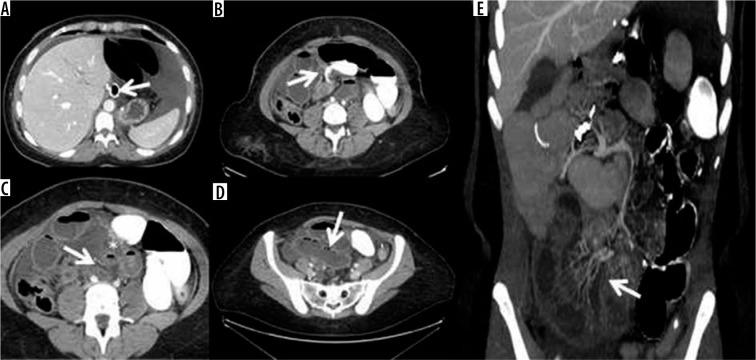

诊断性影像学在减重手术急性并发症诊断中的应用

Diagnostic imaging in the diagnosis of acute complications of bariatric surgery.

The aim of study is to identify the frequency of acute complications and imaging findings at gastro-intestinal transit (GI) and computerised tomography (CT) in a group of obese patients who developed clinical suspicion of acute complications (painful and meteoric abdomen, nausea, vomiting, fever, intestinal blockage) in post bariatric surgery.

MATERIAL AND METHODS

We retrospectively review 954 obese patients who underwent bariatric surgery between 2013 and 2019. The study included 72 patients who developed clinical suspicion of acute complications (painful and meteoric abdomen, nausea, vomiting, fever, intestinal blockage) within 6 days of bariatric surgery of sleeve gastrectomy, gastric banding, gastric bypass with Roux loop confirmed by CT, and who underwent a gastrointestinal transit before the CT examination.

RESULTS

GI exam allowed visualisation of 58% of complications. Analysing the data for each surgical technique, 46 post-operative complications were found involve gastric banding. The most frequent was bandage migration (26 cases, 56 %), identified in all cases at GI transit and then confirmed on CT.

CONCLUSIONS

The study suggests that CT should be used to clarify all doubtful or clinically discordant GI transit exam results. The participation of a radiologist in qualification and post-operative evaluation is important for bariatric surgery patients.

本研究旨在确定一组肥胖患者在接受减重手术后出现急性并发症临床疑似症状(腹痛、腹胀、恶心、呕吐、发热、肠梗阻)时,胃肠道造影(GI)和计算机断层扫描(CT)检查中急性并发症的发生率及影像学表现。

材料与方法

我们回顾性分析了2013年至2019年间接受减重手术的954例肥胖患者。该研究纳入了72例在袖状胃切除术、胃束带术、Roux袢胃旁路术后6天内出现急性并发症临床疑似症状(腹痛、腹胀、恶心、呕吐、发热、肠梗阻)且经CT证实,并在CT检查前进行了胃肠道造影的患者。

结果

GI检查能够发现58%的并发症。分析每种手术技术的数据,发现46例术后并发症与胃束带术有关。最常见的是束带移位(26例,56%),所有病例在GI造影时均被发现,随后经CT证实。

结论

该研究表明,对于所有可疑或临床结果不一致的GI造影检查结果,均应使用CT进行明确。放射科医生参与减重手术患者的术前评估和术后评估非常重要。